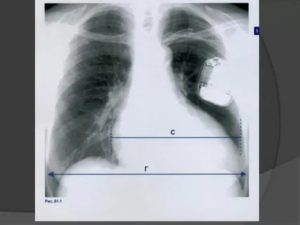

Основным признаком спаечного процесса на легком является наличие тени, которая появилась на снимке. Стоит учесть тот факт, что она никак не изменяет свою форму при вдохе и выдохе. Наряду с этим легочное поле будет менее прозрачным, а диафрагма и грудная клетка могут быть несколько деформированы. Зачастую спайки наблюдаются внизу легкого.

Достоверная визуальная диагностика плевральных шварт возможна только если соединительно-тканные образования больше 1 см в толщину. В противном случае тень от спаек накладывается на ткань легкого и не видна на рентгенограмме. При указании на характерные жалобы, которые возникли и сохраняются после перенесенного плеврита, требуется проведение дополнительных исследований таких, как:

При тотальных швартах наблюдается деформация грудной клетки, сужение межреберных промежутков, смещение средостения в больную сторону, искривление позвоночника в здоровую сторону.

Для обнаружения легочных заболеваний в первую очередь используется флюорография. Эту процедуру необходимо проводить ежегодно, в основном она направлена на выявление ранней стадии туберкулеза. Однако опытный рентгенолог может выявить на снимке образовавшиеся плевральные спайки, которые выглядят тенями. Причем форма их не меняется в зависимости от вдоха и выдоха.

При необходимости дополнительно назначается рентген. Как правило, спайки располагаются в нижней части легкого. При этом будет более темная картинка, а также может быть частичная деформация грудной клетки и диафрагмы.

Основной атрибут, указывающий на спайку справа, является тень, видная на Rg-снимке. При этом затемнение не изменяется при вдохе и выдохе пациента. Одновременно снижается прозрачность легочной поверхности.

В тяжелых случаях наблюдается деформирование грудной клетки и диафрагмальной области. При таком состоянии диафрагма ограничивает свою подвижность. Чаще всего такие спайки расположены в нижних отделах легкого.

Распознать спайку по снимкам можно, если на нем легкие мутные, а еще при сравнении фотографий на вдохе и на выдохе. Спайка выглядит как тень, положение которой не меняется во время дыхания. Иногда наблюдается изменение формы и ограничение подвижности диафрагмы и грудной клетки.

Чаще всего спайки обнаруживают в нижней части легких.